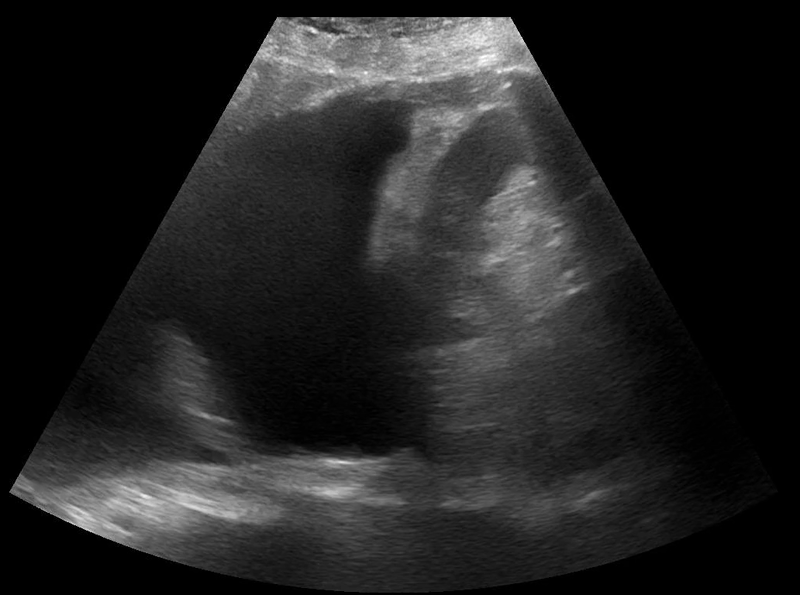

Image 2: POCUS thoracic of the left hemidiaphragm with a positive ‘spine sign.’